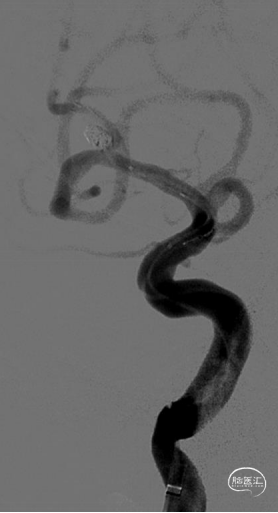

最后全释放支架,序贯撤出微导管,造影可见支架打开完全、贴壁完美,载瘤动脉角度变化小,管腔通畅,动脉瘤Raymond 1级栓塞。

术后即刻给予波立维300mg,第二天口服波立维75mg+拜阿司匹林100mg。术后给予低分子肝素抗凝2天,恢复良好,1周后出院,尚未造影复查。

本例患者动脉瘤位于大脑中动脉分叉上干起始部,载瘤动脉分叉角度锐利,上干与M1段管腔直径变化大。

采用常规支架势必会显著改变载瘤动脉形态,术中动脉瘤破裂、载瘤动脉损伤,支架贴壁性、长期载瘤动脉保持通畅等问题难以解决。

Atlas支架开环设计,血管直径跨度大时支架贴壁性能好,顺应血管走形轴向柔顺性好,并且输送导管细利于超选择插管,释放顺滑定位准确,术后支架展示对血管影响细微,非常适合此类病例使用。